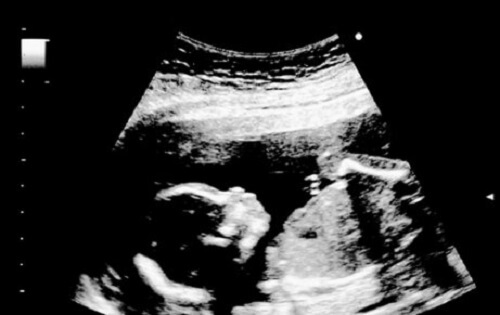

Under en ultralyd kan du observere at babyen strekker seg og strekker armer og ben. Du kan også se fosteret åpne og lukke munnen når han eller hun lærer å svelge.

På grunn av gjennomsiktigheten i babyens hud er blodkarene synlig. Øyevipper og øyenbryn begynner også å vises, og barnets øyne og ører inntar sin faste stilling. I en ultralyd kan foreldre få sjansen til å se babyen suge på fingrene.

Et 18 uker gammelt foster gjesper og lager grimaser. Noen opplever til og med hikke under svangerskapet. Når et foster har hikke, kan han eller hun til og med hoppe i livmoren.